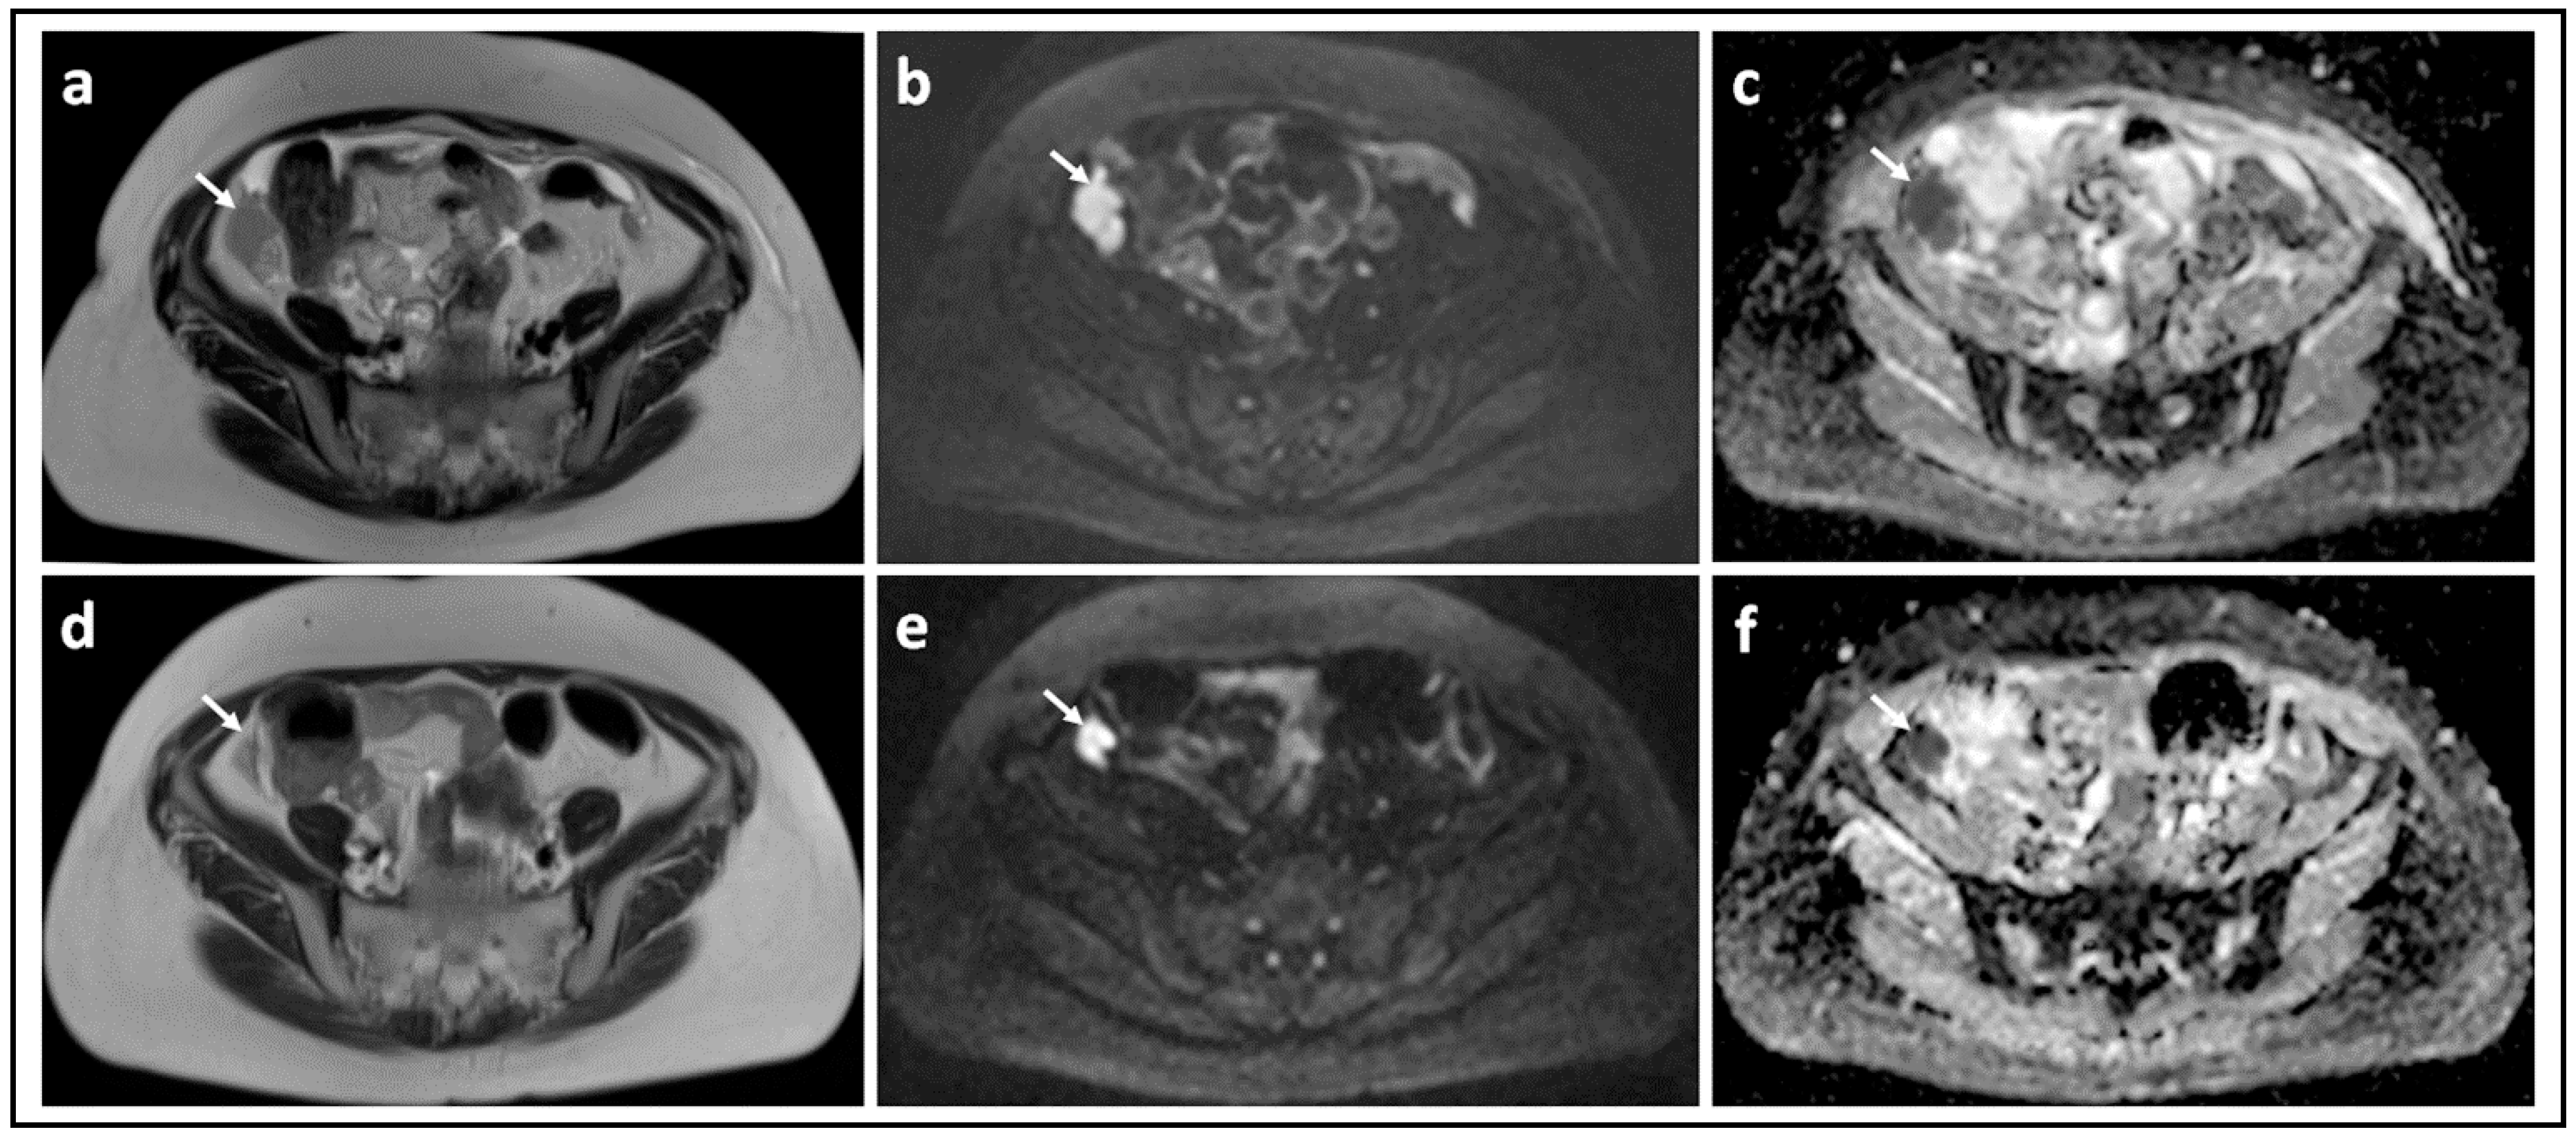

Figure 1.

Peritoneal metastases in high grade serous ovarian cancer showing increasing lesion conspicuity with increasing b-value: T2-W (a) and DW-MRI at b-values of 0 s/mm2 (b), 100 s/mm2 (c), 500 s/mm2 (d), and 900 s/mm2 (e). The irregular metastatic deposits on the surface of the bowel and in the mesentery (arrows) show diffusion restriction. They increase in conspicuity and contrast as diffusion weighting increases because they retain signal while signal from adjacent normal tissues diffuses away.

Figure 4.

Omental cake showing marked response to chemotherapy: T2-W image (a) and corresponding b = 900 s/mm2 DW-MRI (b) and ADC map (c) through the mid-pelvis in a patient with high grade serous ovarian cancer before treatment shows a large omental cake in the anterior pelvis. It is recognized by its homogenous solid appearance and marked diffusion restriction (arrows). Corresponding slices of T2-W (d), b = 900 s/mm2 DW-MRI (e) and ADC map (f) after three cycles of platinum-based chemotherapy illustrate that the omental cake is no longer identifiable.

Figure 5.

Peritoneal metastasis showing poor response to chemotherapy: T2-W image (a) and corresponding b = 900 s/mm2 DW-MRI (b) and ADC map (c) through the upper pelvis in a patient with high grade serous ovarian cancer before treatment shows an irregular right-sided peritoneal metastasis. It is recognized by its homogenous solid appearance and marked diffusion restriction [arrows]. Corresponding slices of T2-W (d), b = 900 s/mm2 DW-MRI (e) and ADC map (f) after three cycles of platinum-based chemotherapy illustrate that there has been marginal reduction in the size of this lesion.